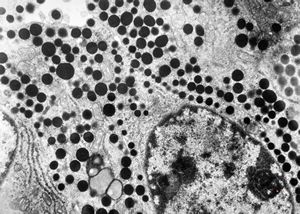

F, 72y. | carcinoid … metastasis to lymphonode